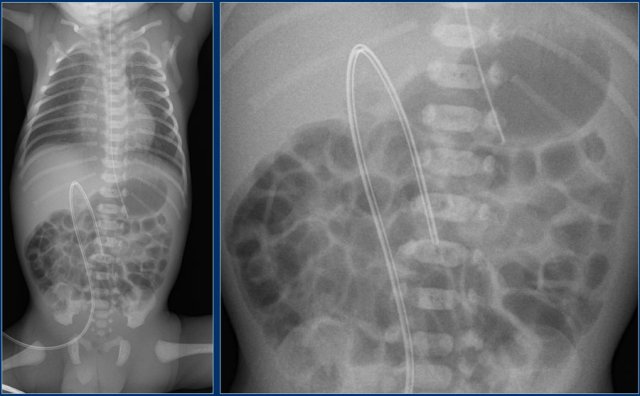

Umbilical artery line (5)

First study the images.

Then continue reading.

The findings are:

1. Malposition of umbilical artery line in left iliac artery.

2. Deep position of umbilical vein line in right atrium.

3. Good position of gastric tube.